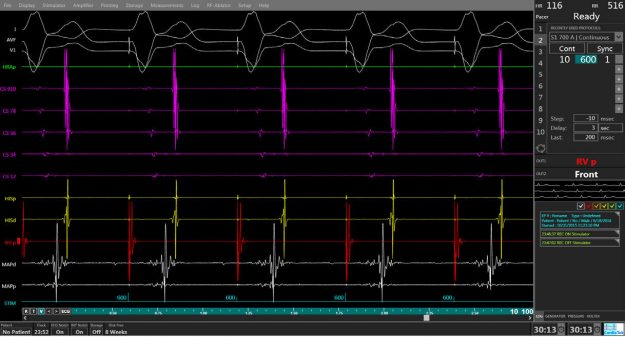

Holter rythmique (ou Holter ECG)

Interview du Dr Laurent Fiorina, rythmologue à l’ICPS et spécialiste de l’analyse digitalisée des tracés de rythme cardiaque puisqu’il travaille également pour la société Cardiologs, start up française qui a développé une solution utilisant l’intelligence artificielle pour faciliter l’analyse des Holter rythmiques Comment marche un Holter rythmique ? Notre cœur fonctionne avec un système…